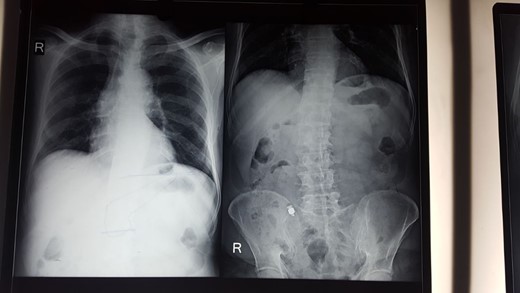

After diagnostic laparoscopy small bowel revealed a stricture in the terminal ileum 3 feet proximal to the ileocecal valve. With the help of C-arm machine video capsule identified (Fig. 2).